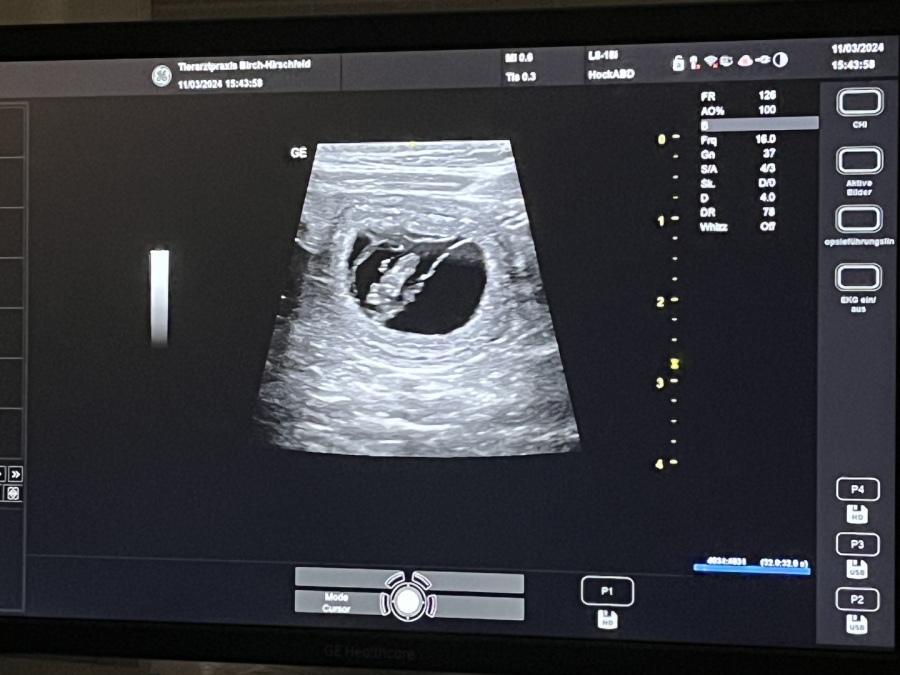

Der Ultraschall hat es bestätigt, Mitte April erwartet Dorie ihren 2. Wurf.

Man konnte auch schon die kleinen Herzchen schlagen sehen. Es ist immer wieder ein Wunder.